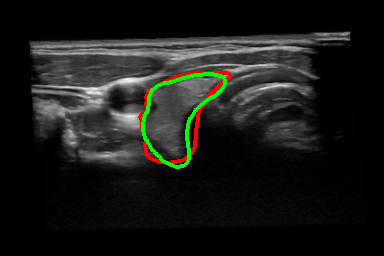

Thyroid Segmentation: The thyroid data used in this experiment has been acquired from a publicly available dataset [3] which includes freehand acquired thyroid US volumes from healthy human subjects imaged with a MHz probe. The proposed approach is compared with four different algorithms which has been reported by Narayan et. al. [1], (Table. 2). The only limitation in trying to compare commonality is that the dataset used for this comparison is not the same as the dataset used in prior art [1]. 2D visualization of segmentation is shown in Fig. 3(k) - (n) and the thyroid segmentation in the whole volume is visualized 11footnotemark: 1. Table 2 shows that our proposed frame work obtain better results than the prior art.